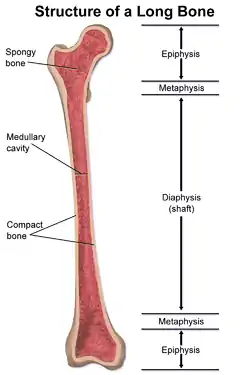

Structure of a long bone, with epiphysis labeled at top and bottom. | |

An epiphysis (from Ancient Greek ἐπί (epí) 'on top of', and φύσις (phúsis) 'growth'; pl.: epiphyses) is one of the rounded ends or tips of a long bone that ossify from a secondary center of ossification.[3][4] Between the epiphysis and diaphysis (the long midsection of the long bone) lies the metaphysis, including the epiphyseal plate (growth plate). At the joint, the epiphysis is covered with articular cartilage; below that covering is a zone similar to the epiphyseal plate, known as subchondral bone.

The epiphysis is filled with red bone marrow, which produces erythrocytes (red blood cells).